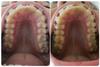

Всем привет! 3 месяца очень быстро пролетели) Щели наконец-то почти закрылись, осталось совсем чуть-чуть, это радует Еще спилили надкусочные пломбы, такое облегчение)

Не радует перекос, единички на разном уровне и еще несколько вещей. Орт на все мои замечания говорит "все хорошо" . Ну ничего, я подожду, пока щели закроются, и возможно буду искать нового